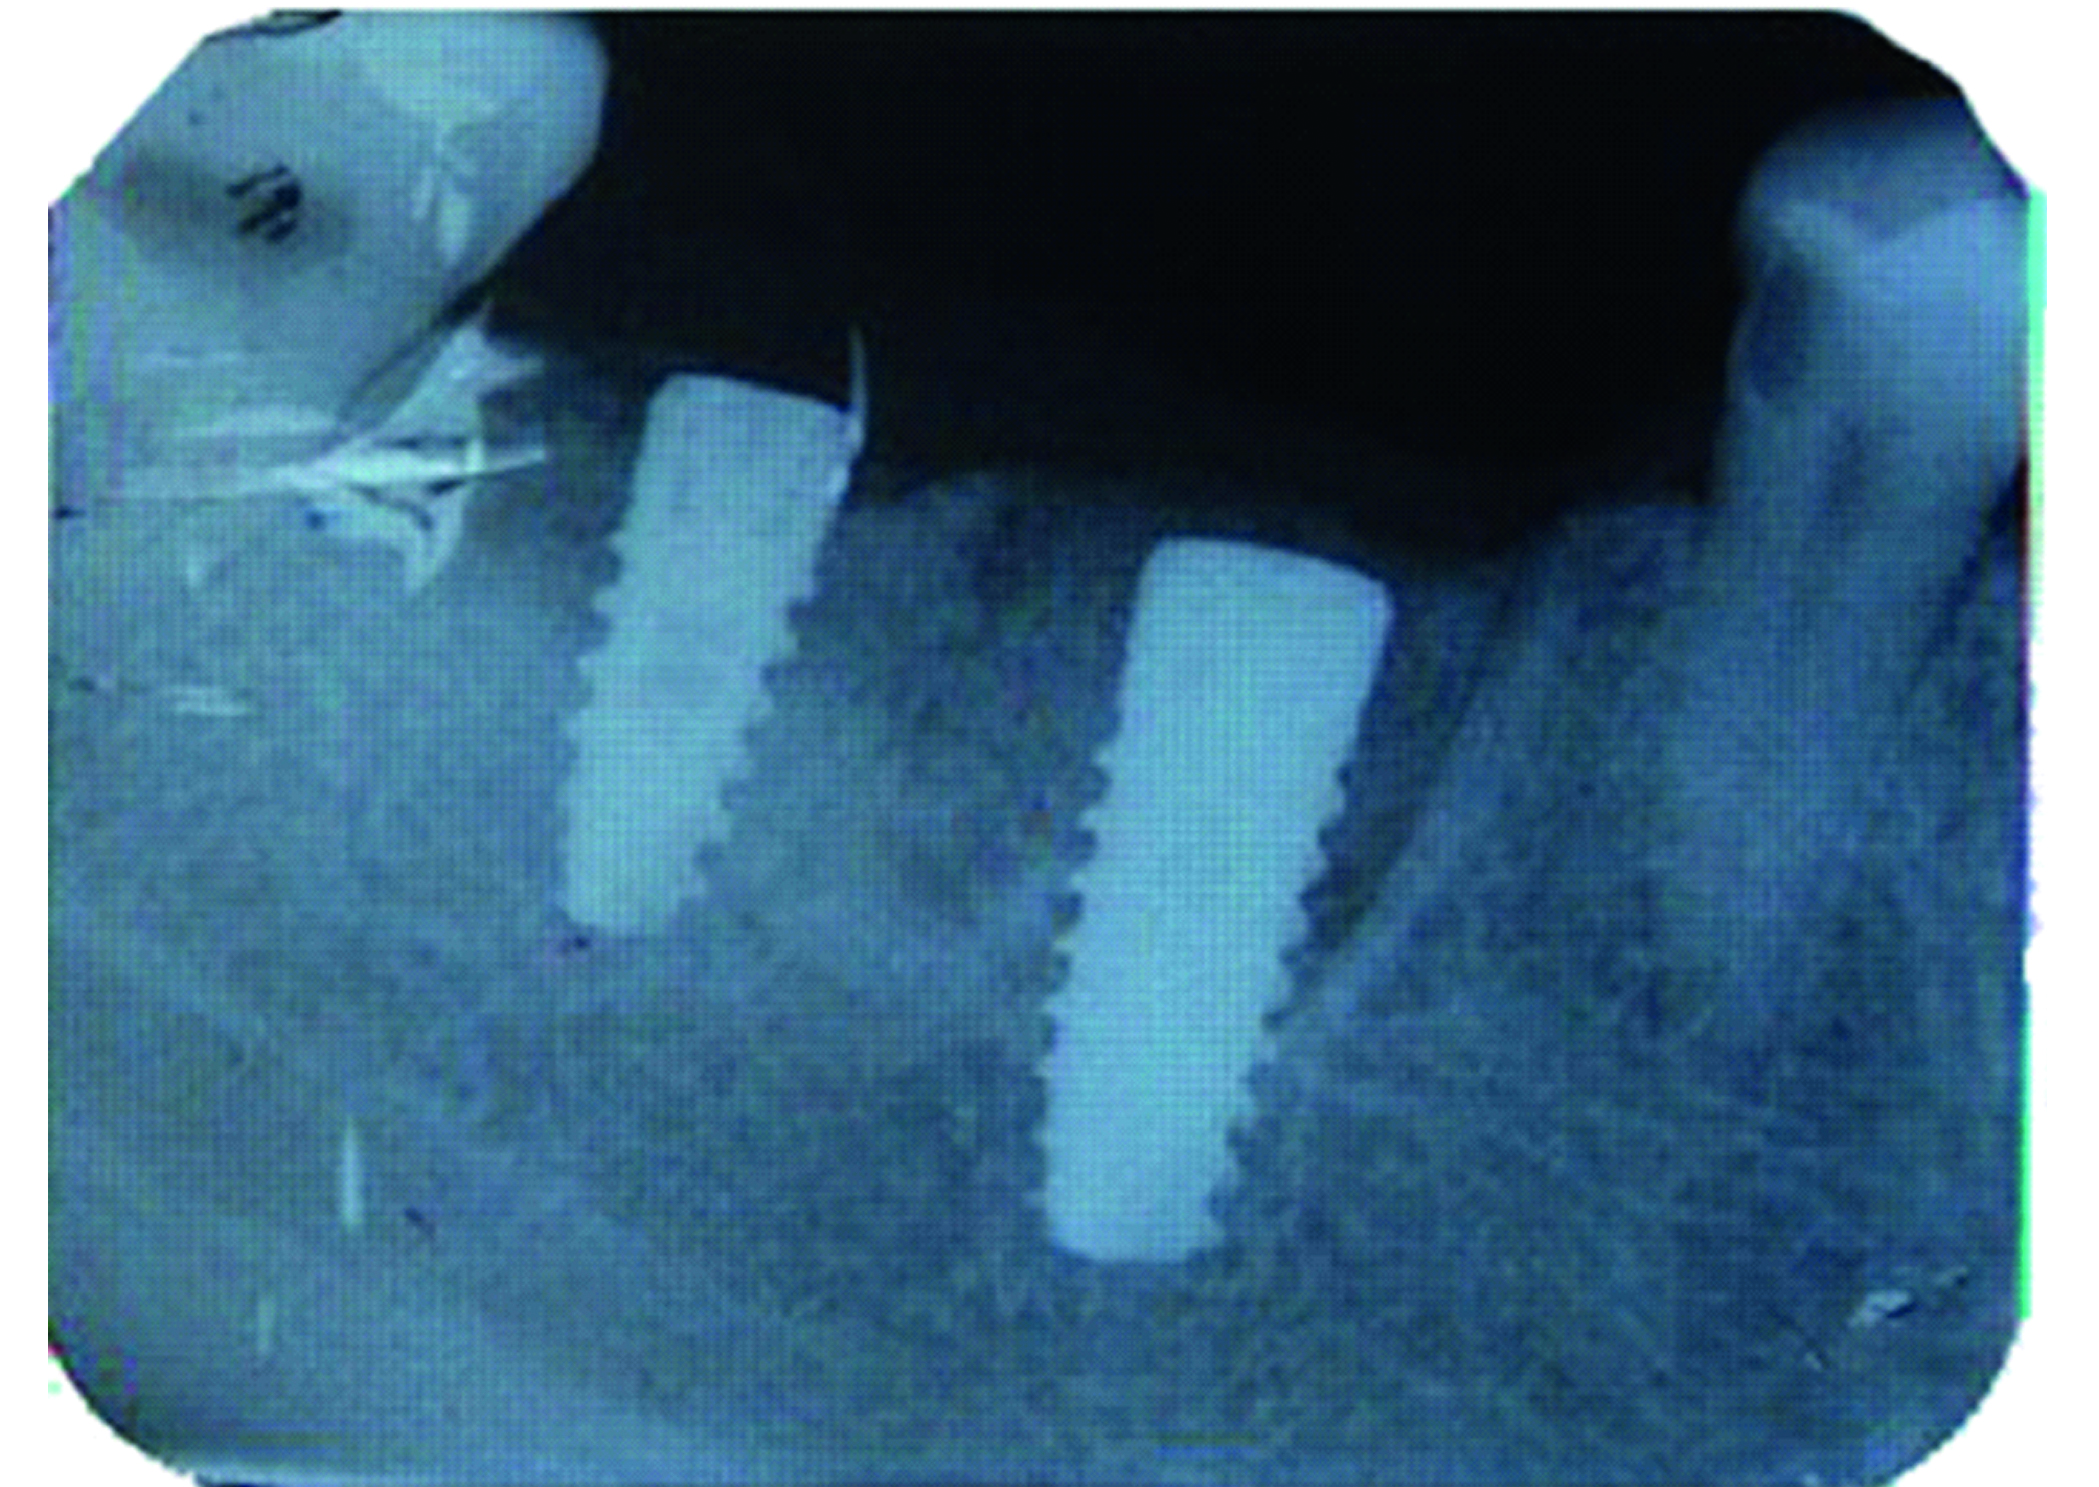

Атравматичное удаление позволило сохранить все стенки альвеолы и межкорневую перегородку, что в свою очередь способствовало первичной стабилизации установленного имплантата (рисунки 2, 3).

Рисунок 2. Установка дентальных имплантатов в области ранее удаленных зубов 4.6, 4.7.

Рисунок 3. Рентгенограмма области установленных имплантатов.